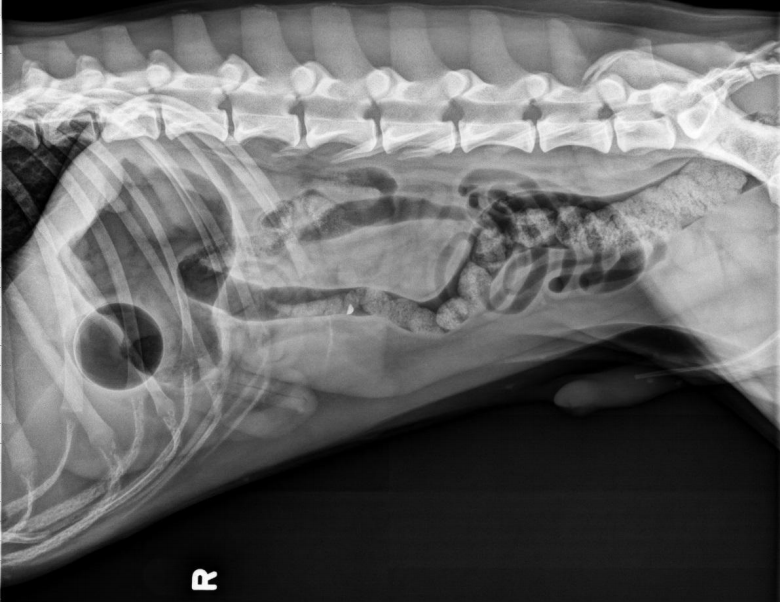

●6 mo female Great Dane

●Vomiting, loss of appetite for 3 days

●Suspected foreign body

● Entire small intestine moderately homogenously fluid filled, teeny bubbles throughout GI tract indicating GI hypomotility.

● Markedly gas-distended intestinal segment in mid-abdomen, reverse C-shaped, most likely normal caecum.

● Diffusedly fluid filled GIT with interspersed gas bubbles is most consistent with functional ileus from severe enteritis.

● No radiographically evident foreign body.

● Dx: Parvoviral enteritis